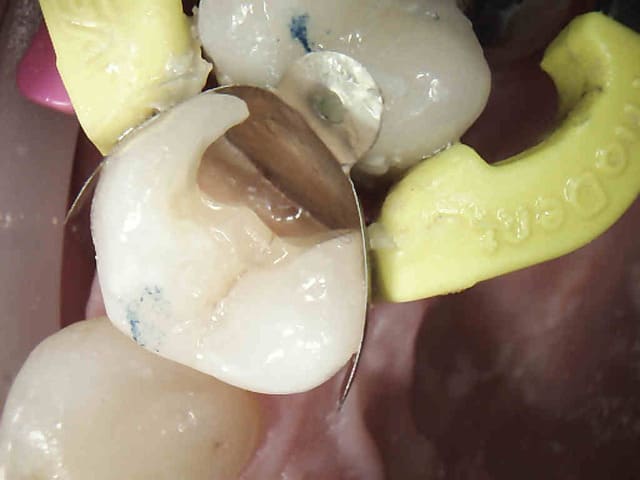

Et je termine la semaine avec un no post no crown; Le récipoc m'a un peu démangé je dois dire, mais ca n'est peut être que partie remise.-)))

N'en jetez plus c'est surtout la matrice qui est bonne. -))))

personnellement j'aurais fait le composite avant la couronne, pas de problème de contacte et contrôle du composite qui a fusé dans la concavité de la racine

Ben justement j'ai refait le composite parce qu'il y avait un problème de point de contact avec la couronne. Sur ce genre de cas le patient ne se plaignant pas j'ai tendance à fidéliser. Mais c'est sur il vaut mieux ne pas prendre de radios après les composites des fois on est décu, mais c'est trop tard.-))))